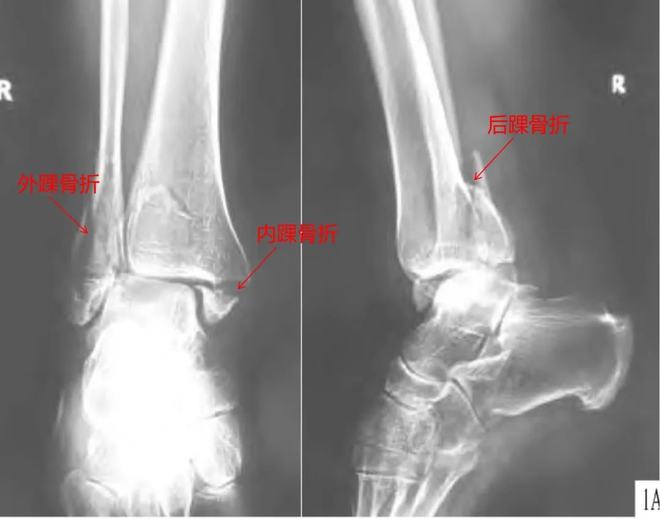

筆者的三踝骨折是踝關(guān)節(jié)骨折中比較嚴(yán)重的一種類型,三踝骨折除了內(nèi)外踝骨折外,還合并脛骨遠(yuǎn)端后踝骨折,是一種嚴(yán)重而復(fù)雜的關(guān)節(jié)內(nèi)骨折,通常伴有踝關(guān)節(jié)脫位。對(duì)于像筆者這樣不能進(jìn)行急診手術(shù)的三踝骨折合并踝關(guān)節(jié)脫位患者,通常需要先將脫位復(fù)位,石膏固定,待腫脹消退后再進(jìn)行手術(shù),這樣可以有效保留踝關(guān)節(jié)功能。

三踝骨折X光圖丨參考1

踝部骨折手術(shù)的最佳時(shí)機(jī)是什么時(shí)候?一般來說,手術(shù)的最佳時(shí)間是受傷后6小時(shí)內(nèi),即踝部明顯腫脹、水泡出現(xiàn)之前。此時(shí)緊急手術(shù)切開、復(fù)位、固定骨折,可減少血腫,利于切口一期縫合,從而減少患者痛苦,縮短住院時(shí)間。